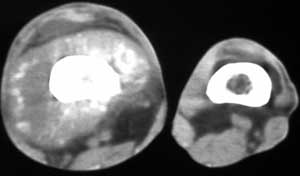

男56涨疼5-6月

右股骨下端包绕股骨见巨大软组织肿块,密度部俊,周围见瘤骨,下端骨皮质侵蚀变薄,骨质周围无骨膜反应, 考虑右股骨软骨肉瘤。

右股骨下段周围软组织肿块伴钙化,相邻股骨骨皮质受累,考虑软组织来源恶性病变

右股骨下段骨肉瘤,软组织内瘤骨,软组织肿块。